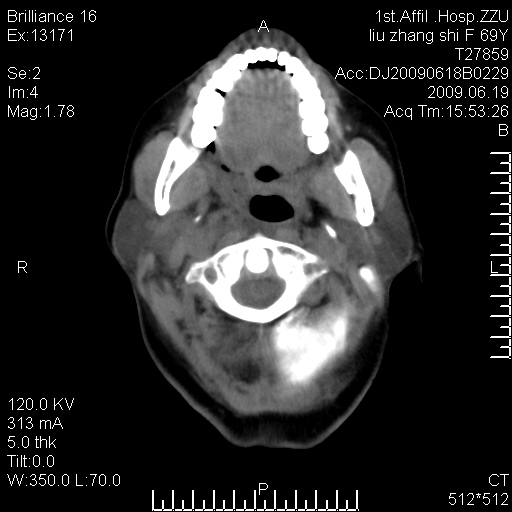

标题: CT26782:女,69岁,颈部占位,3天后公布病理结果。

【病理证实系列】女,69岁,颈部占位,有病理结果,3天后公布。(由于病例时间较久,临床资料不全,请网友见谅)本系列将有几百种常见、少见及罕见病例,均经病理证实。病例资料来自郑州大学第一附属医院。与网友共享,本人有空就发。

鉴别:淋巴瘤、恶性神经源性病变、恶性纤维组织细胞瘤。

病理结果:颈部非霍奇金淋巴瘤。